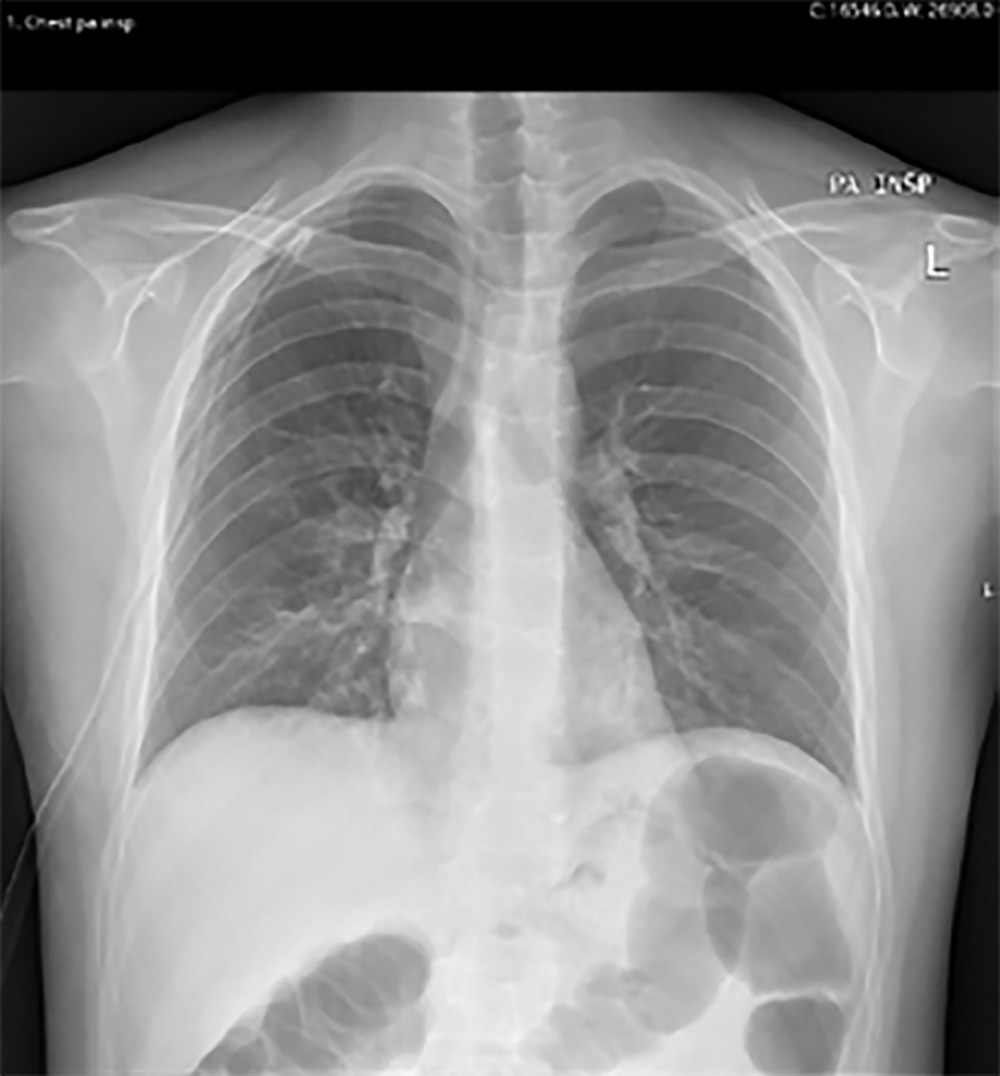

Após a observação da radiografia e aplicação das guidelines da BTS, optou-se por colocar o doente sob oxigenoterapia suplementar e discutiu-se o caso com os médicos de cirurgia geral. Optou-se pela realização de toracotomia no hemitórax direito sob anestesia local, sendo confirmada a correta colocação do dreno com recurso a nova radiografia do tórax (Fig. 2). De acordo com as indicações da BTS o dreno utilizado foi de 18 Fr associado a um selo d´água do dreno. Para além das recomendações da BTS o tamanho definido para o dreno a colocar foi decido considerando a menor probabilidade de obstrução de um dreno deste calibre, relativamente a um de calibre inferior.

Confirmou-se, igualmente, a saída de ar do dreno (sinal que se encontra funcionante), ausência de evidente pneumotórax e de enfisema subcutâneo resultantes da colocação do mesmo.